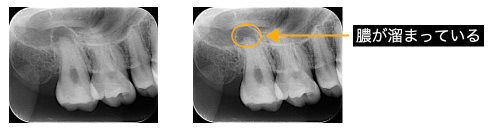

①根の先に膿が溜まっている

根の先の歯茎を押すと痛い、歯茎にできものができて膿が出る。

そのような時は根管治療が必要となります。